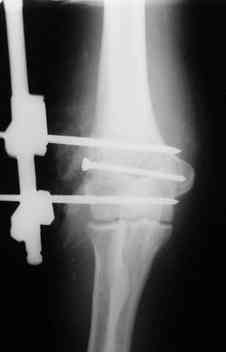

Уважаемые коллеги! Мужчина, 49 лет, упал 2 недели назад, будучи около полугода в запое. Сразу припоступлении рана промыта а-ля пульсирующая струя" до 8 литров и стабилизация (без ушивания раны). Через 2 дня пациент покинул отделение, думаю, что сражался с рогатыми животными, еще через 4 дня победив всех врагов пришел как путный с поникшей головой. На настоящий момент рана с обильным гнойным отделяемым в виде комков, но повязка стала промокать меньше, температура субфебрильная 4 дня и выше 37,3 не поднималась, боли умеренные, больше ночью. Есть несколько вопросов: 1.Нужна ли сейчас ревизия и дебридмент? 2.Оптимальный вариант дренирования? (сейчас просто резиновые выпускники, в т.ч. через онтраппертуру). 3.Нижний стержень находиться в очаге. Его необходимо убрать? Если да, то вариант фиксации.Жалко свою работу. Может общими усилиями спасем? ;) Спасибо. С уважением, Алексей.

Если нет нагноения его канала, то убирать его не надо. Однако фиксация не сильно надежная, может, хоть задней гипсовой шиной дополнить. Или наложить секцию на предплечье.

Уважаемые коллеги. Внешний вид конечности через 5 недель после травмы. Рана гранулирует, отделяемое скудное. Прошу строго не судить за внешний вид АВФ: ну нет пока у нас параллельных зажимов (приходиться выкручиваться).